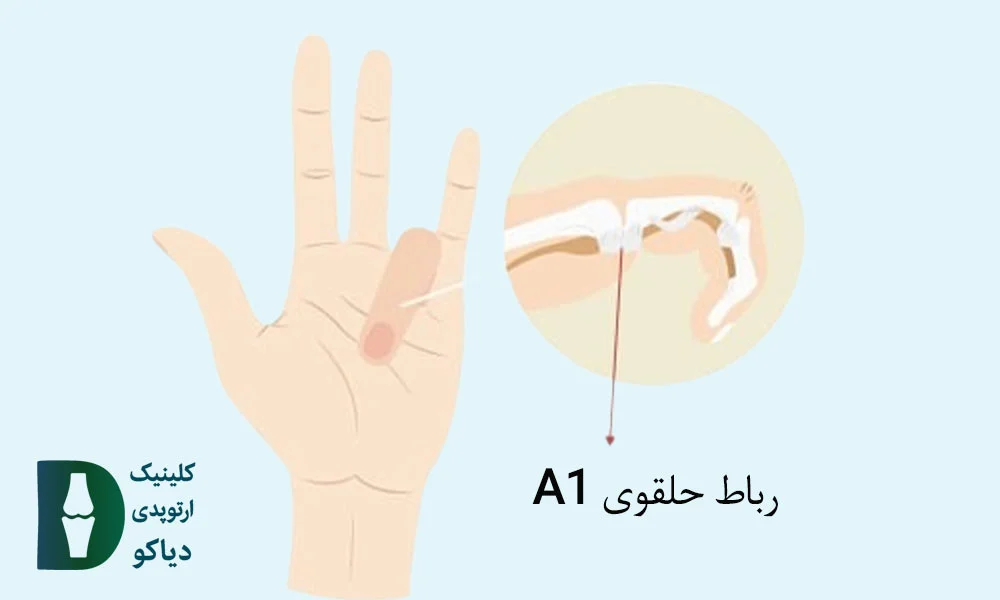

در بزرگسالان، انگشت ماشهای اغلب بهدلیل التهاب و ضخیمشدن غلاف تاندون خمکننده (بهویژه در ناحیهی A1 pulley ) ایجاد میشود؛ وضعیتی که باعث گیر کردن تاندون در مسیر حرکتش شده و هنگام باز یا بسته کردن انگشت، احساس قفلشدگی، صدای تق یا درد بهوجود میآورد.

در بیماران با گرید 2 و 3a، که انگشت هنگام حرکت دچار قفلشدگی میشود ولی هنوز قابلیت صافشدن دارد (چه بهصورت فعال یا با کمک دست دیگر)، درمانهای غیرجراحی میتوانند بسیار مؤثر باشند و از پیشرفت بیماری یا نیاز به جراحی جلوگیری کنند. در این مراحل، هدف درمان، کاهش التهاب غلاف تاندون، بهبود حرکت تاندون درون رباط حلقوی A1 و پیشگیری از چسبندگیهای بیشتر است.

تزریق کورتون معمولاً در محل غلاف تاندون A1 در پایه انگشت، نزدیک سر استخوان کفدستی انجام میشود.

تزریق داروی کورتون (معمولاً تریامسینولون یا دگزامتازون) در ناحیهی غلاف تاندون A1، درست بالای استخوان کفدستی (متاکارپال)، میتواند التهاب را کاهش دهد و حرکت تاندون خمکننده را تسهیل کند. این درمان در بیماران با انگشت ماشهای گرید 2 و 3a معمولاً بسیار مؤثر است. اغلب بیماران طی ۳ تا ۷ روز بهبود قابلتوجهی در درد و گیرکردن انگشت تجربه میکنند. در اکثر موارد، یک نوبت تزریق کافی است؛ اما در موارد مقاوم، ممکن است نیاز به تزریق دوم نیز وجود داشته باشد.

عمل جراحی معمولاً بهصورت سرپایی و با بیحسی موضعی انجام میشود. جراح با ایجاد یک برش کوچک در کف دست، رباط حلقوی A1 را که تاندون را تحت فشار قرار داده، برش میدهد تا مسیر حرکت تاندون باز و بدون اصطکاک شود. این فرایند معمولاً کمتر از ۲۰ دقیقه زمان میبرد و نیاز به بستریشدن در بیمارستان ندارد.